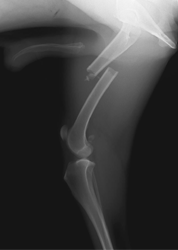

■ 症例2

極小犬(体重1.3㎏)の橈尺骨骨折

ロッキングプレート(TITAN LOCK)による固定